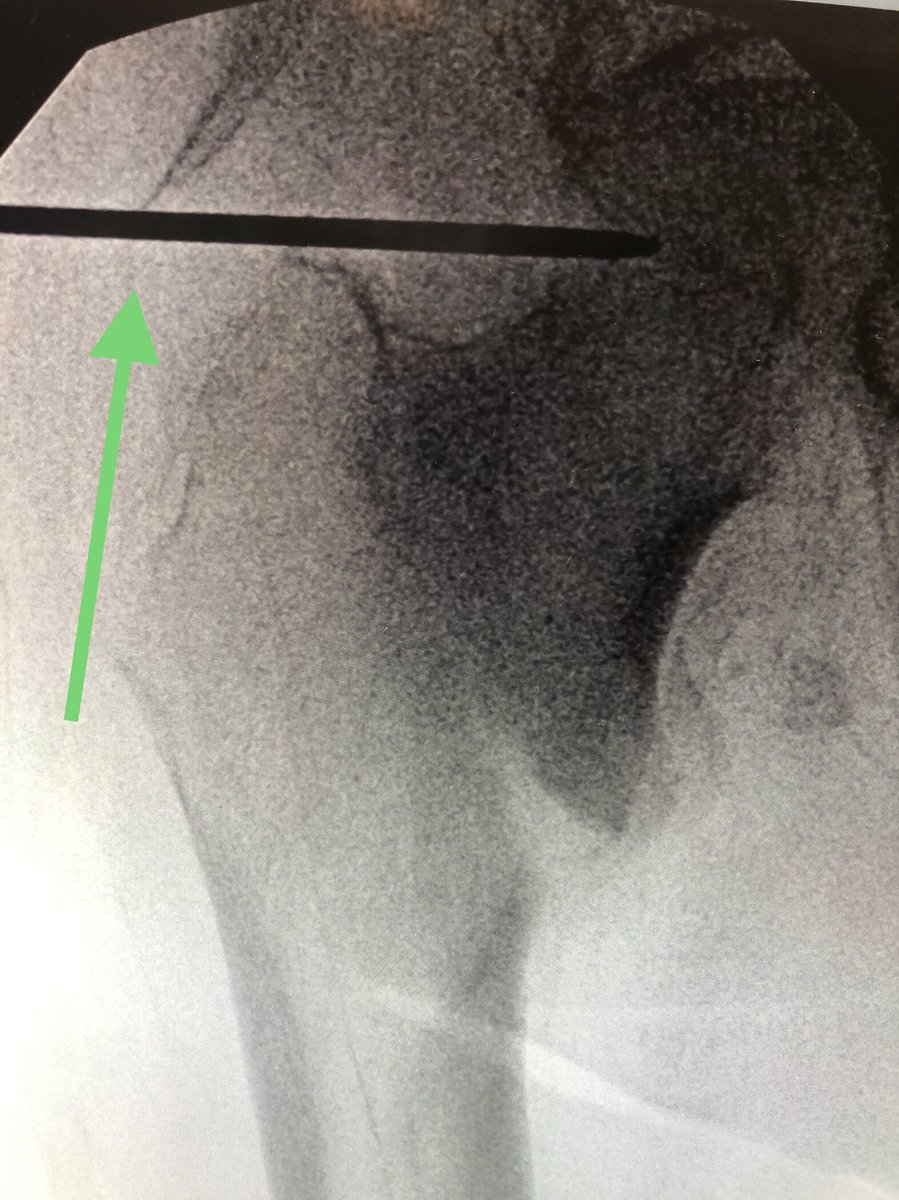

[18/18] The troch fragment is little abducted here, I don’t worry so much about screw being close to fracture line because nails don’t rely on lateral wall to work. Keep TAD (or calTAD as I do) small and most ITs heal without an issue. I also don’t use blades. Thanks for reading!